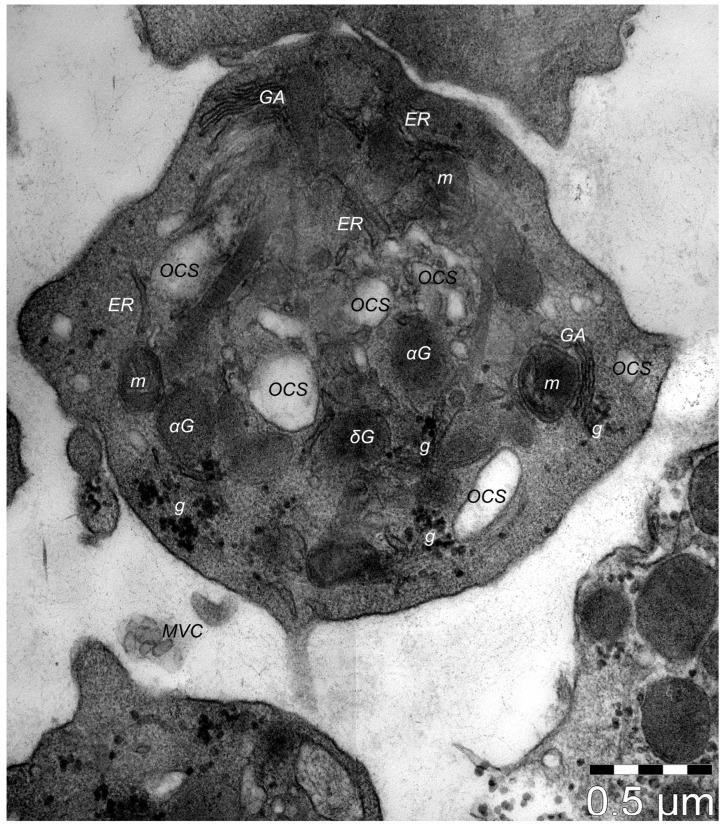

For more than 40 years, autologous platelet concentrates have been used in clinical medicine. Since the first formula used, namely platelet-rich plasma (PRP), other platelet concentrates have been experimented with, including platelet-rich fibrin and concentrated growth factor. Platelet concentrates have three standard characteristics: they act as scaffolds, they serve as a source of growth factors and cytokines, and they contain live cells. PRP has become extensively used in regenerative medicine for the successful treatment of a variety of clinical (non-)dermatological conditions like alopecies, acne scars, skin burns, skin ulcers, muscle, cartilage, and bone repair, and as an adjuvant in post-surgery wound healing, with obvious benefits in terms of functionality and aesthetic recovery of affected tissues/organs. These indications were well documented, and a large amount of evidence has already been published supporting the efficacy of this method. The primordial principle behind minimally invasive PRP treatments is the usage of the patient's own platelets. The benefits of the autologous transplantation of thrombocytes are significant, representing a fast and economic method that requires only basic equipment and training, and it is biocompatible, thus being a low risk for the patient (infection and immunological reactions can be virtually disregarded). Usually, the structural benefits of applying PRP are attributed to fibroblasts only, as they are considered the most numerous cell population within the interstitium. However, this apparent simplistic explanation is still eluding those different types of interstitial cells (distinct from fibroblasts) that are residing within stromal tissue, e.g., telocytes (TCs). Moreover, dermal TCs have an already documented potential in angiogenesis (extra-cutaneous, but also within skin), and their implication in skin recovery in a few dermatological conditions was attested and described ultrastructurally and immunophenotypically. Interestingly, PRP biochemically consists of a series of growth factors, cytokines, and other molecules, to which TCs have also proven to have a positive expression. Thus, it is attractive to hypothesize and to document any tissular collaboration between cutaneous administered PRP and local dermal TCs in skin recovery/repair/regeneration. Therefore, TCs could be perceived as the missing link necessary to provide a solid explanation of the good results achieved by administering PRP in skin-repairing processes.